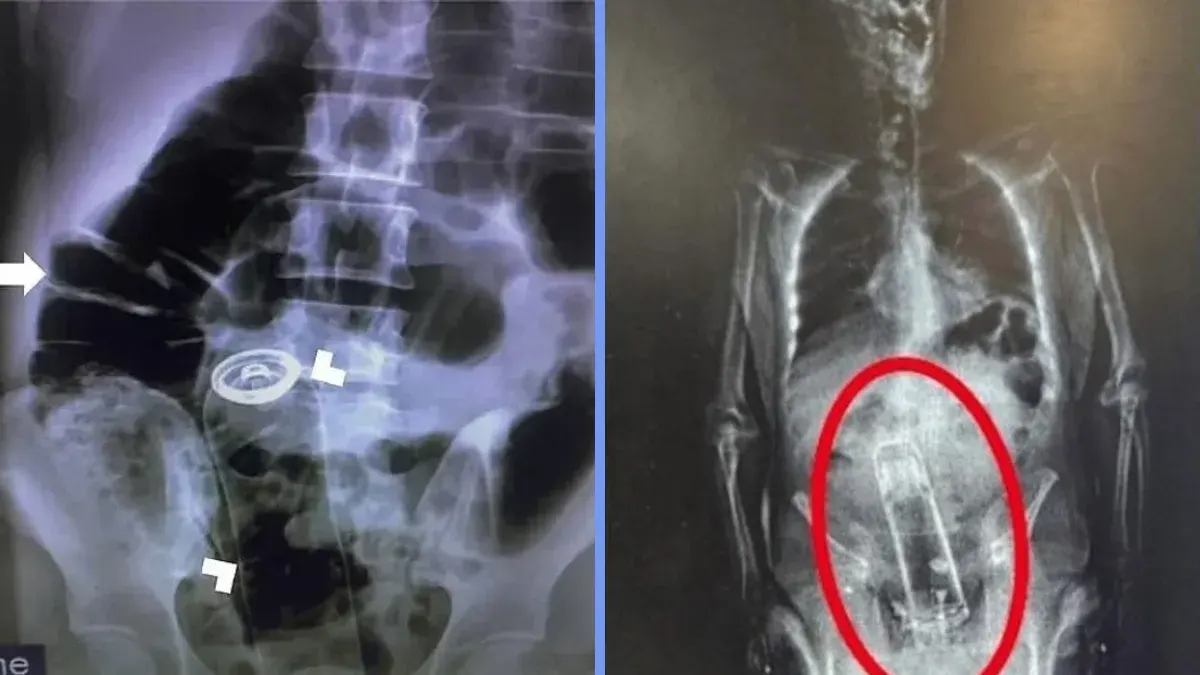

เรื่องราวที่ฟังดูเหมือนมุกตลกแต่กลับเป็นวิกฤตสุขภาพที่เกิดขึ้นจริง เมื่อฐานข้อมูลทางการแพทย์เปิดเผยสถิติสุดช็อกของผู้ป่วยที่ต้องหามส่งห้องฉุกเฉินเพราะมี "สิ่งแปลกปลอม" เข้าไปติดค้างอยู่ในทวารหนัก ซึ่งสิ่งของเหล่านั้นมีตั้งแต่ของใช้ในบ้านไปจนถึงอุปกรณ์ช่างที่คาดไม่ถึง จนกลายเป็นอุทาหรณ์เตือนใจเรื่องความประมาทและความเสี่ยงที่เป็นอันตรายถึงชีวิต

จากบันทึกของคณะกรรมการความปลอดภัยสินค้าอุปโภคบริโภคแห่งสหรัฐฯ (CPSC) พบว่าในปีที่ผ่านมามีกรณีผู้ป่วยเข้าห้องฉุกเฉินด้วยสาเหตุนี้เป็นจำนวนมาก แม้ผู้ป่วยส่วนใหญ่มักจะให้เหตุผลกับแพทย์ว่าเกิดจากอุบัติเหตุล้มทับโดยไม่ตั้งใจ แต่รายการสิ่งของที่แพทย์ดึงออกมาได้นั้นกลับสะท้อนถึงการทำกิจกรรมที่ผิดพลาดหรือการทดลองที่ขาดความระมัดระวัง

โดยรายการสิ่งของที่สร้างความตกตะลึงให้กับทีมแพทย์ประกอบด้วย:

หมวดของกินและเครื่องครัว: เช่น ไข่ไก่, พาสต้าดิบ, ที่เสียบข้าวโพด และจุกปิดขวดไวน์

หมวดของใช้ในบ้าน: ตั้งแต่หลอดไฟ, ไฟฉาย, ลูกบิดประตู, ไปจนถึงแว่นตาและรองเท้าแตะ

หมวดอุปกรณ์ช่าง: ที่น่ากลัวที่สุดคือ ตะปู, สกรู และคีม ซึ่งบางเคสผู้ป่วยพยายามใช้คีมเพื่อดึงวัตถุอื่นออกมาเองแต่กลับทำให้ติดค้างเข้าไปเพิ่ม

ของเบ็ดเตล็ด: เช่น ลูกเบสบอล หรือแม้แต่บุหรี่ไฟฟ้า

ดร. เคนจิ โอยาสุ แพทย์ผู้เชี่ยวชาญด้านห้องฉุกเฉินระบุว่า หนึ่งในเคสที่น่าตกใจที่สุดคือการพบ "เทียนหอมขนาดใหญ่" ติดค้างอยู่ทั้งขวด ซึ่งอันตรายของการนำวัตถุแปลกปลอมใส่เข้าไปคือการเกิด "แรงดูดสุญญากาศ" ทำให้วัตถุถูกดูดลึกเข้าไปจนไม่สามารถดึงออกเองได้ตามธรรมชาติ หากปล่อยไว้อาจนำไปสู่การติดเชื้อ เนื้อเยื่อตาย หรือลำไส้ทะลุ

จากสถิติพบว่ากลุ่มผู้ป่วยหลักกว่าร้อยละ 78 เป็นเพศชาย วัยทำงาน และกว่าร้อยละ 40 ของเคสที่เข้ารับการรักษาจำเป็นต้องนอนโรงพยาบาลหรือรับการผ่าตัดใหญ่เพื่อนำวัตถุออก เนื่องจากสถานการณ์มักจะแย่ลงเมื่อผู้ป่วยพยายามใช้อุปกรณ์อื่นงัดแงะออกเองจนเกิดบาดเจ็บรุนแรง